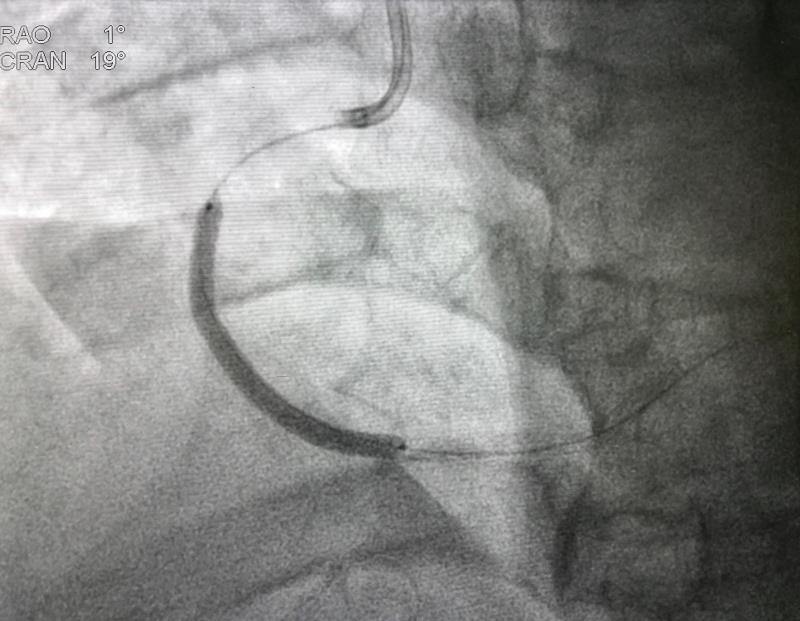

Patients with ST-elevation myocardial infarction (STEMI) who undergo primary percutaneous coronary intervention (PCI) have a reduced risk of all-cause death or BARC* type 3–5 bleeding when they receive a bolus plus post-PCI high-dose infusion of bivalirudin compared with heparin monotherapy, results of the BRIGHT**-4 trial showed.

The multicentre (87 sites in China), open-label trial included 6,016 patients (median age 61 years, 21.5 percent female) with STEMI undergoing primary PCI with radial access within 48 hours of symptom onset. They were randomized 1:1 to receive bivalirudin (0.75 mg/kg bolus followed by 1.75 mg/kg/hour infusion for 2–4 hours post-PCI [median 3 hours]) or unfractionated heparin monotherapy (70 IU/kg bolus) during primary PCI.